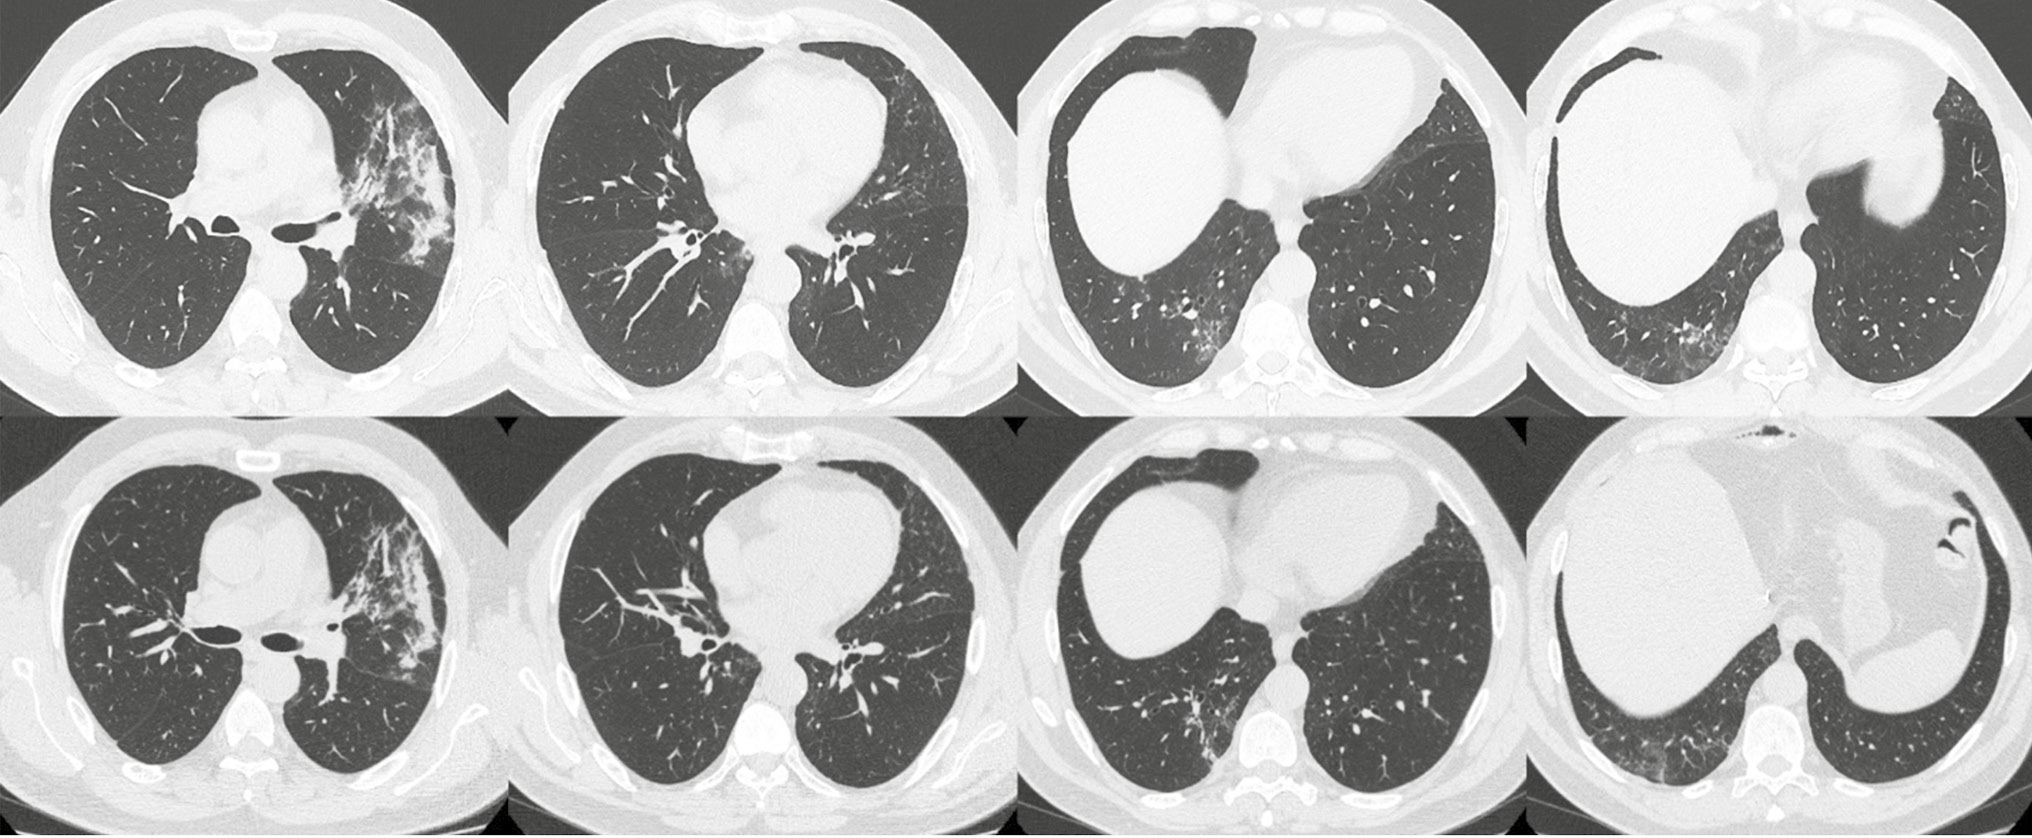

На обзорной рентгенограмме органов грудной клетки от 07.04.2020 выявлены инфильтративные изменения в проекции С4–5 слева. 08.04.2020 выполнена трепан-биопсия трансплантата печени. По данным гистологического исследования: фиброз F1 по Metavir, активность А0–1, слабовыраженный венулит, признаков отторжения трансплантата не выявлено. По результатам компьютерной томографии (КТ) органов брюшной полости и грудной клетки от 14.04.2020 в 3, 6, 10-м сегментах левого легкого и в 6, 7, 10-м сегментах правого легкого выявлены участки инфильтрации по типу «матового стекла» различной степени интенсивности и консолидации легочной ткани, участки тяжистого уплотнения, мелкие ретикулярные изменения (рис. 1).

Рис. 1. Пациент, 54 года: данные компьютерной томографии органов грудной клетки от 14 апреля 2020 г. при плановом обследовании

Клинический диагноз: Двусторонняя полисегментарная вирусная пневмония.